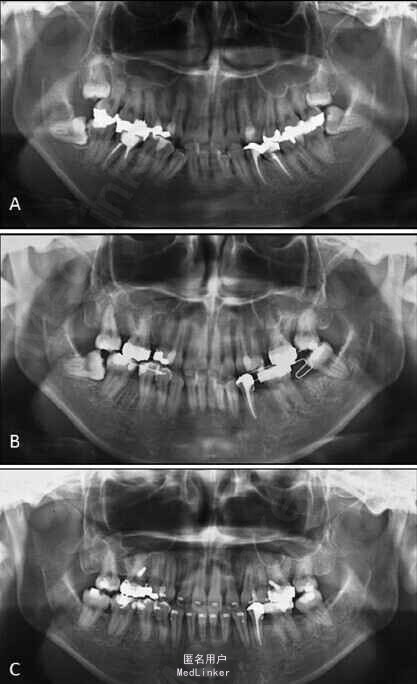

面部:凸面型,上下唇前突,上唇E线前3.5mm,下唇E线前9.5mm,闭唇时口周肌肉紧张。口内检查:双侧尖牙磨牙I类关系,左侧7锁合,覆盖4.5mm,覆合1mm,中线正,上颌拥挤度12.5mm,下颌拥挤度8.2mm。全景片示4个第三磨牙均阻生,怀疑上颌第二磨牙远中面因8阻生有牙根吸收,下颌8近中倾斜阻生更严重,右下6、左下4和5都行了RCT并大面积充填。头影测量示骨性I类,高角,下切牙唇倾。无TMJ症状,只是咀嚼测试时,右侧(非锁合侧)较左侧速度更快且更稳定。

诊断:安氏II类1分类,双颌前突,牙列严重拥挤,左下7锁合,双侧上7牙根吸收,四颗第三磨牙阻生 治疗目标:减少唇的突度及前牙拥挤,扶正4颗阻生的第三磨牙,达到良好的面部美观和功能咬合。 治疗:上颌拔除2颗5和2颗7(不拔4的原因为左上4为正常牙,左上5大面积充填;右上4形态较右上5好。因拔除了坏牙保留了健康牙齿,但是拔5不利于前牙的内收,所以于上后牙56之间植入了支抗钉加强支抗,辅助内收前牙。拔7原因为两颗7远中面均有牙根吸收且有大面积充填),下颌左侧拔除5和7(左下5根管治疗且根尖阴影,拔除左下7原因为严重锁合,改正困难且容易导致上下磨牙的伸长加重II类高角面型),右侧拔除根管治疗且大面积充填后的6;分别竖直4颗近中倾斜阻生的8,整个疗程39个月,四颗8成功的代替6或7。双侧I类尖牙关系,左侧磨牙I类关系,右侧磨牙完全远中关系。唇突度改善,全景片可见达到可接受的牙根平行度,4个8完全萌出直立。以前因为锁合导致的两侧咬合不对称没有了。

用阻生的第三磨牙代替缺损很大的磨牙是保留健康牙齿很有效的方法。患者1年后5个月随访,效果依然稳定。